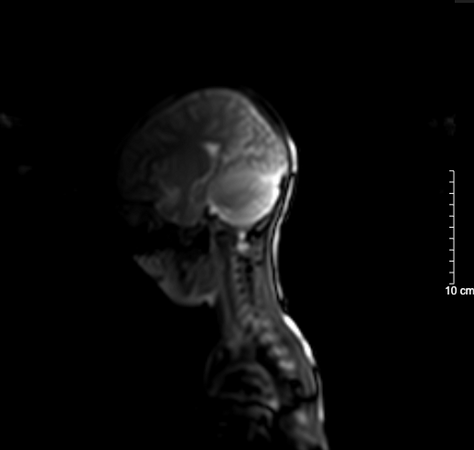

1746787230117.png1746787250787.png

Kết quả chụp não, cột sống cổ bệnh nhi sau 5 ngày nhập viện bình thường

BSCKII. Doãn Phúc Hải - Trung tâm Nhi khoa, Bệnh viện Bạch Mai trực tiếp điều trị cho bệnh nhi chia sẻ: Thân nhiệt của bệnh nhi được hạ nhanh xuống và kiểm soát duy trì ở mức 34°C, giảm tổn thương, tái tưới máu tại não, tăng tỉ lệ sống và hồi phục chức năng thần kinh. Sau 72 giờ điều trị hạ thân nhiệt chủ động, bệnh nhi được nâng thân nhiệt, làm ấm trở lại về mức bình thường và duy trì theo dõi trong 48 giờ. Khi thân nhiệt trở lại bình thường, bệnh nhi tỉnh dần và được rút ống thở. Dấu hiệu sinh tồn ổn định, tri giác nhận thức tốt. Sau 5 ngày nằm viện, bệnh nhi đã tỉnh táo hoàn toàn. Kết quả chụp tim, phổi, MRI sọ não, cột sống cổ không thấy bất thường. Đây cũng là trường hợp đầu tiên trẻ 5 tuổi tự “thắt cổ” mà chúng tôi bắt gặp.